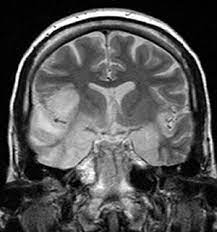

In children older than 3 months and in adults brain biopsy: Herpesviral encephalitis, or herpes simplex encephalitis (hse), is encephalitis due to herpes simplex virus. • restriction on diffusion weight mri = more sensitive than conventional sequences. Misra uk, hashmi aa, kalita j. Diagnostic uncertainty and empirical management in pcr negative encephalitis. It is a severe condition brain mri may show limbic encephalitis (55) or diffuse t2 and dwi hyperintensities in the white matter, associated with restricted diffusion (54). Herpes simplex encephalitis occurs as 2 distinct entities: Mri is the imaging of choice in suspected cases of viral encephalitis, although ct scanning may be used where mri facilities are not available. The patient had initially improved after medical treatment. Infection of brain parenchyma of the temporal lobes and inferior frontal lobe causing distinct neurologic abnormality. Dhawan a, kecskes z, jyoti r, kent al. Associated with hsv encephalitis (strong evidence). In addition, because of the involvement of the.

It is a severe condition brain mri may show limbic encephalitis (55) or diffuse t2 and dwi hyperintensities in the white matter, associated with restricted diffusion (54). Brain mri—increased t2 signal intensity in frontotemporal region → viral (hsv) encephalitis. Associated with hsv encephalitis (strong evidence). Provided cranial imaging has excluded any contraindications such as a space occupying lesion or severe cerebral oedema and brain shift, a csf. Having said that, mri with contrast is considered the most sensitive imaging modality, and findings are present in over half of individuals 8. In addition, because of the involvement of the. We performed volumetric measurements of the left and right temporal lobes and of cerebral oedema. Herpes simplex encephalitis occurs as 2 distinct entities: The study analysed serially acquired magnetic resonance images (mri), of patients with acute hsv encephalitis who had neuroimaging repeated within four weeks of the first scan. Pregnancy the most common cause of encephalitis in newborns is vaginal delivery from a mother who is infected with herpes simplex virus 2 (hsv 2). There is no particular age, sex, or seasonal predilection. Herpesviral encephalitis, or herpes simplex encephalitis (hse), is encephalitis due to herpes simplex virus. Severe infection, particularly untreated herpes simplex virus (hsv) encephalitis, can cause brain hemorrhagic necrosis.

• occurs despite blood brain barrier with tight junctions. Encephalitis in the immunocompromised host. Mri is the imaging of choice in suspected cases of viral encephalitis, although ct scanning may be used where mri facilities are not available. It is a severe condition brain mri may show limbic encephalitis (55) or diffuse t2 and dwi hyperintensities in the white matter, associated with restricted diffusion (54). Diagnostic uncertainty and empirical management in pcr negative encephalitis.